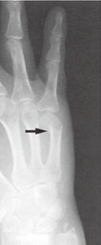

・中手骨骨折:スポーツではボクシング等の格闘技での受傷が多く、別名ボクサー骨折と言われています。特に小指に多くみられます。

中手骨骨折レントゲン像

レントゲン像文献3から

中手骨骨折

多くは保存療法で良好な成績が得られると言われています。転位が大きい場合はワイヤー固定による手術療法を選択することがあります。

中手骨頚部骨折へのワイヤー固定

(Foucher法)